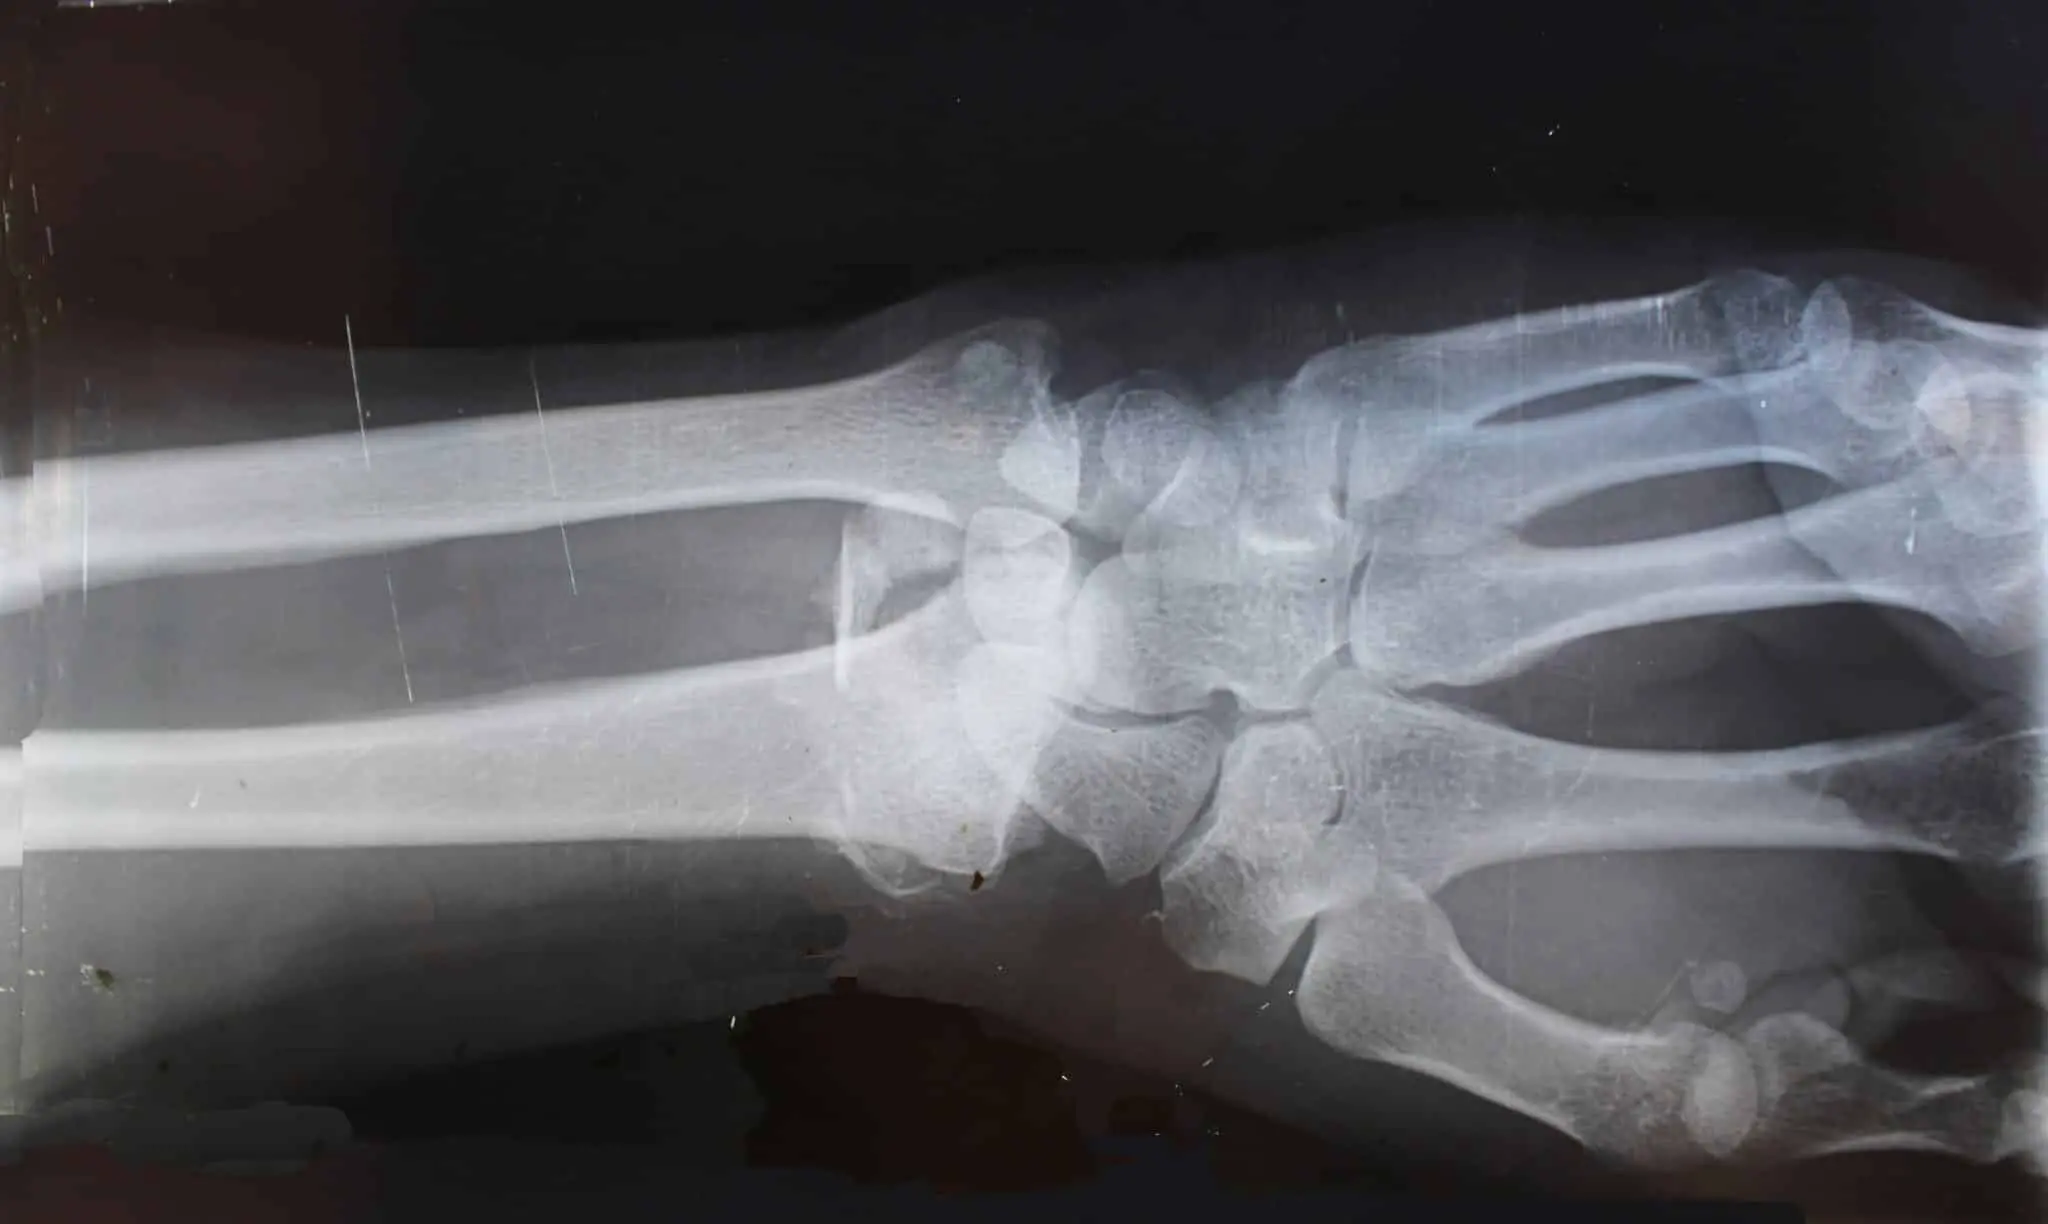

Т-2 токсин — продукт жизнедеятельности грибов Fusarium, активно заражающих злаковые культуры при неблагоприятных условиях хранения. Он способен проникать в человеческий организм через пищу, пораженную грибами, или при прямом контакте с контаминированными продуктами. Токсин разрушает хрящи, провоцирует воспаления и негативно воздействует на жизненно важные органы: сердце, печень, почки и нервную систему. Его опасность усугубляется тем, что он способствует развитию окислительного стресса и нарушает клеточные процессы на фундаментальном уровне.

Исследования, охватившие более двух сотен научных работ последних лет, продемонстрировали, что именно селен способен существенно смягчать повреждающие эффекты Т-2 токсина. При недостатке этого микроэлемента в организме фиксировалось усиление воспалительных реакций, активация процессов повреждения митохондрий, а также ускоренное разрушение клеток хрящевой ткани. В то же время достаточное поступление селена способствовало выработке защитных белков — селенопротеинов, известных своей антиоксидантной активностью. Это разностороннее влияние объясняет, почему селен снижает риск гибели хондроцитов и разобщения межклеточного матрикса.